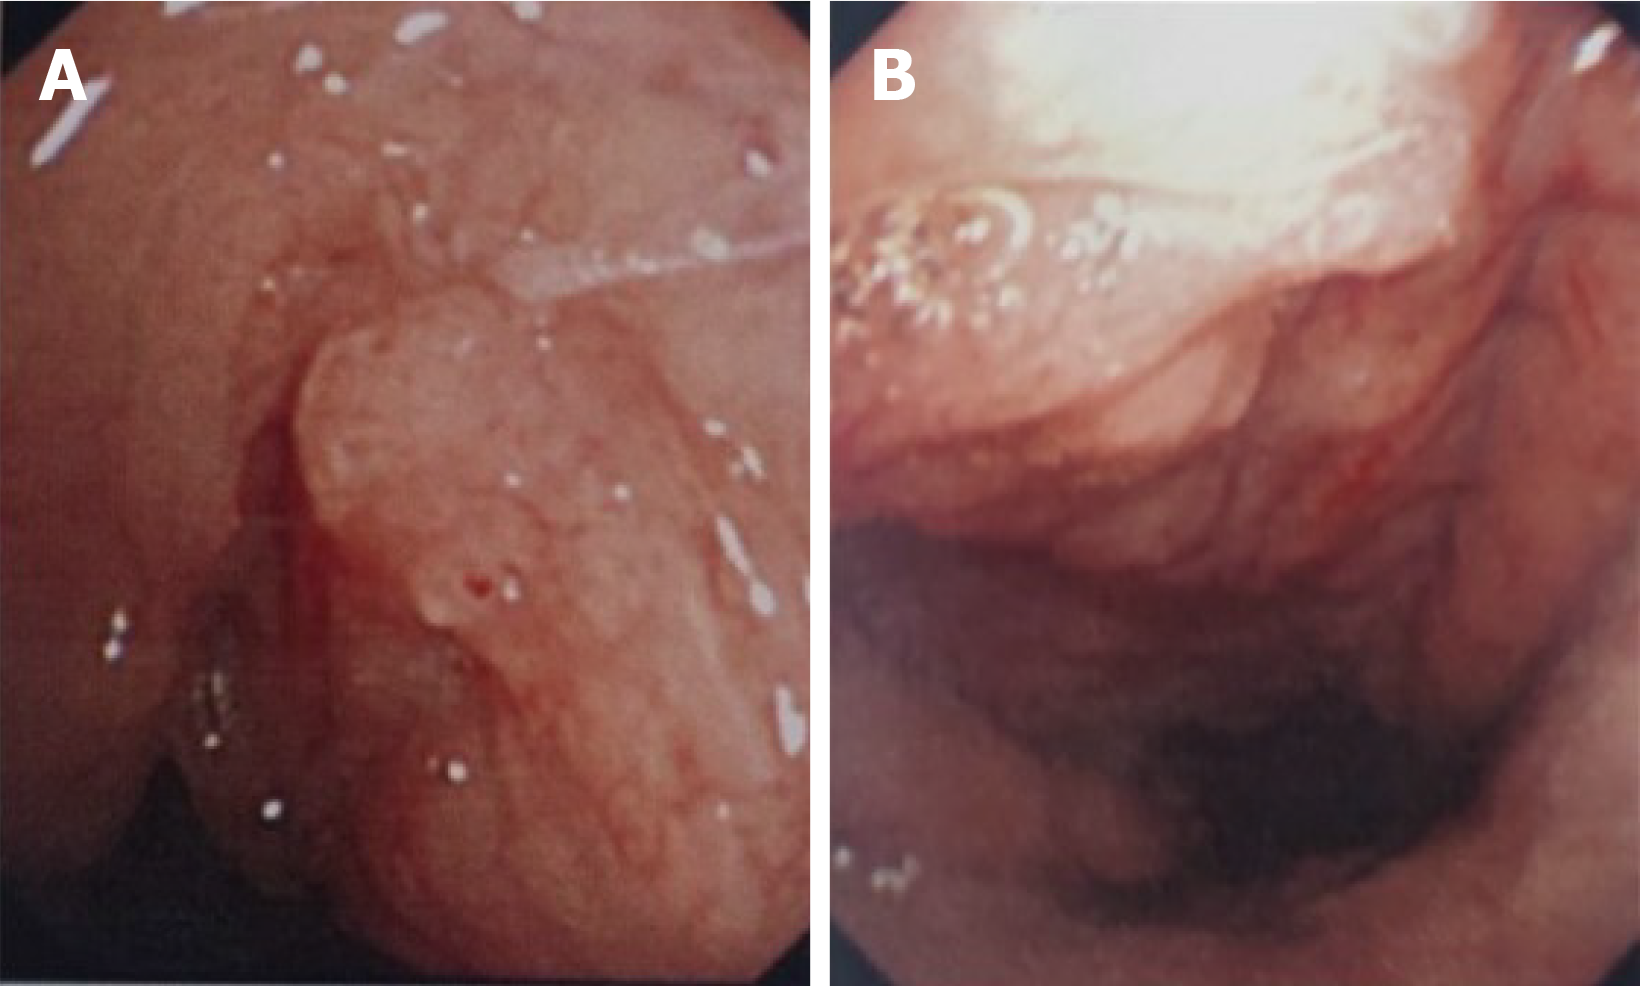

Figure 2 Electronic endoscope images (July 9, 2022).

A: Right pharyngeal recess, tubal torus; B: Nasopharyngeal posterior wall. The nonsmooth new organism is located on the posterior wall of the right nasopharynx, on the right round pillow, and in the pharyngeal recess. The surface of the new organism presents a vascular disorder like appearance.